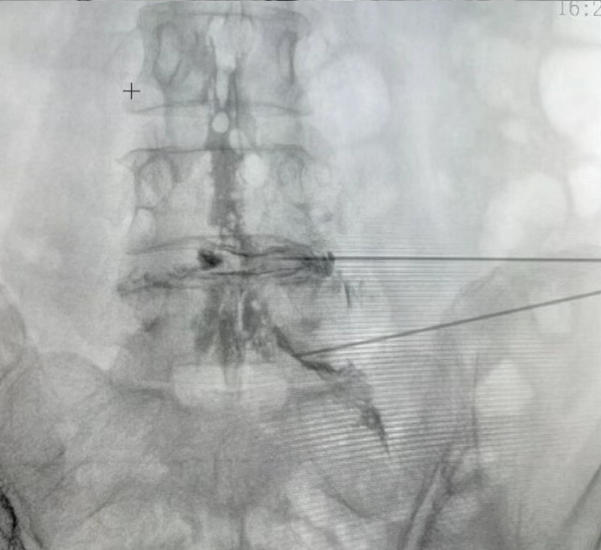

腰椎间盘射频消融联合胶原酶化学溶解术后